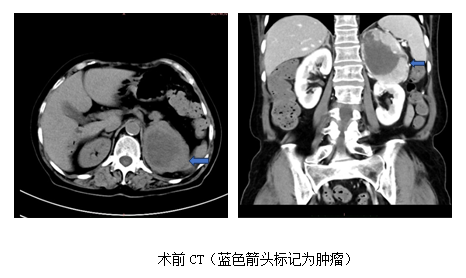

心内科后,赵永勇医师高度重视,予以高血压病因筛查,CT发现左肾上腺区8cm占位,考虑嗜铬细胞瘤可能,肿瘤密度不均匀,显著不均匀强化。同时,查24小时尿儿茶酚胺,显示多巴胺,去甲肾上腺素,甲氧基去甲肾上腺素3甲氧酪胺及香草扁桃酸升高数倍,目前西北区域仅三级片

开展的131I-MIBG检查显示左侧肾上腺区域明显阳性病灶,